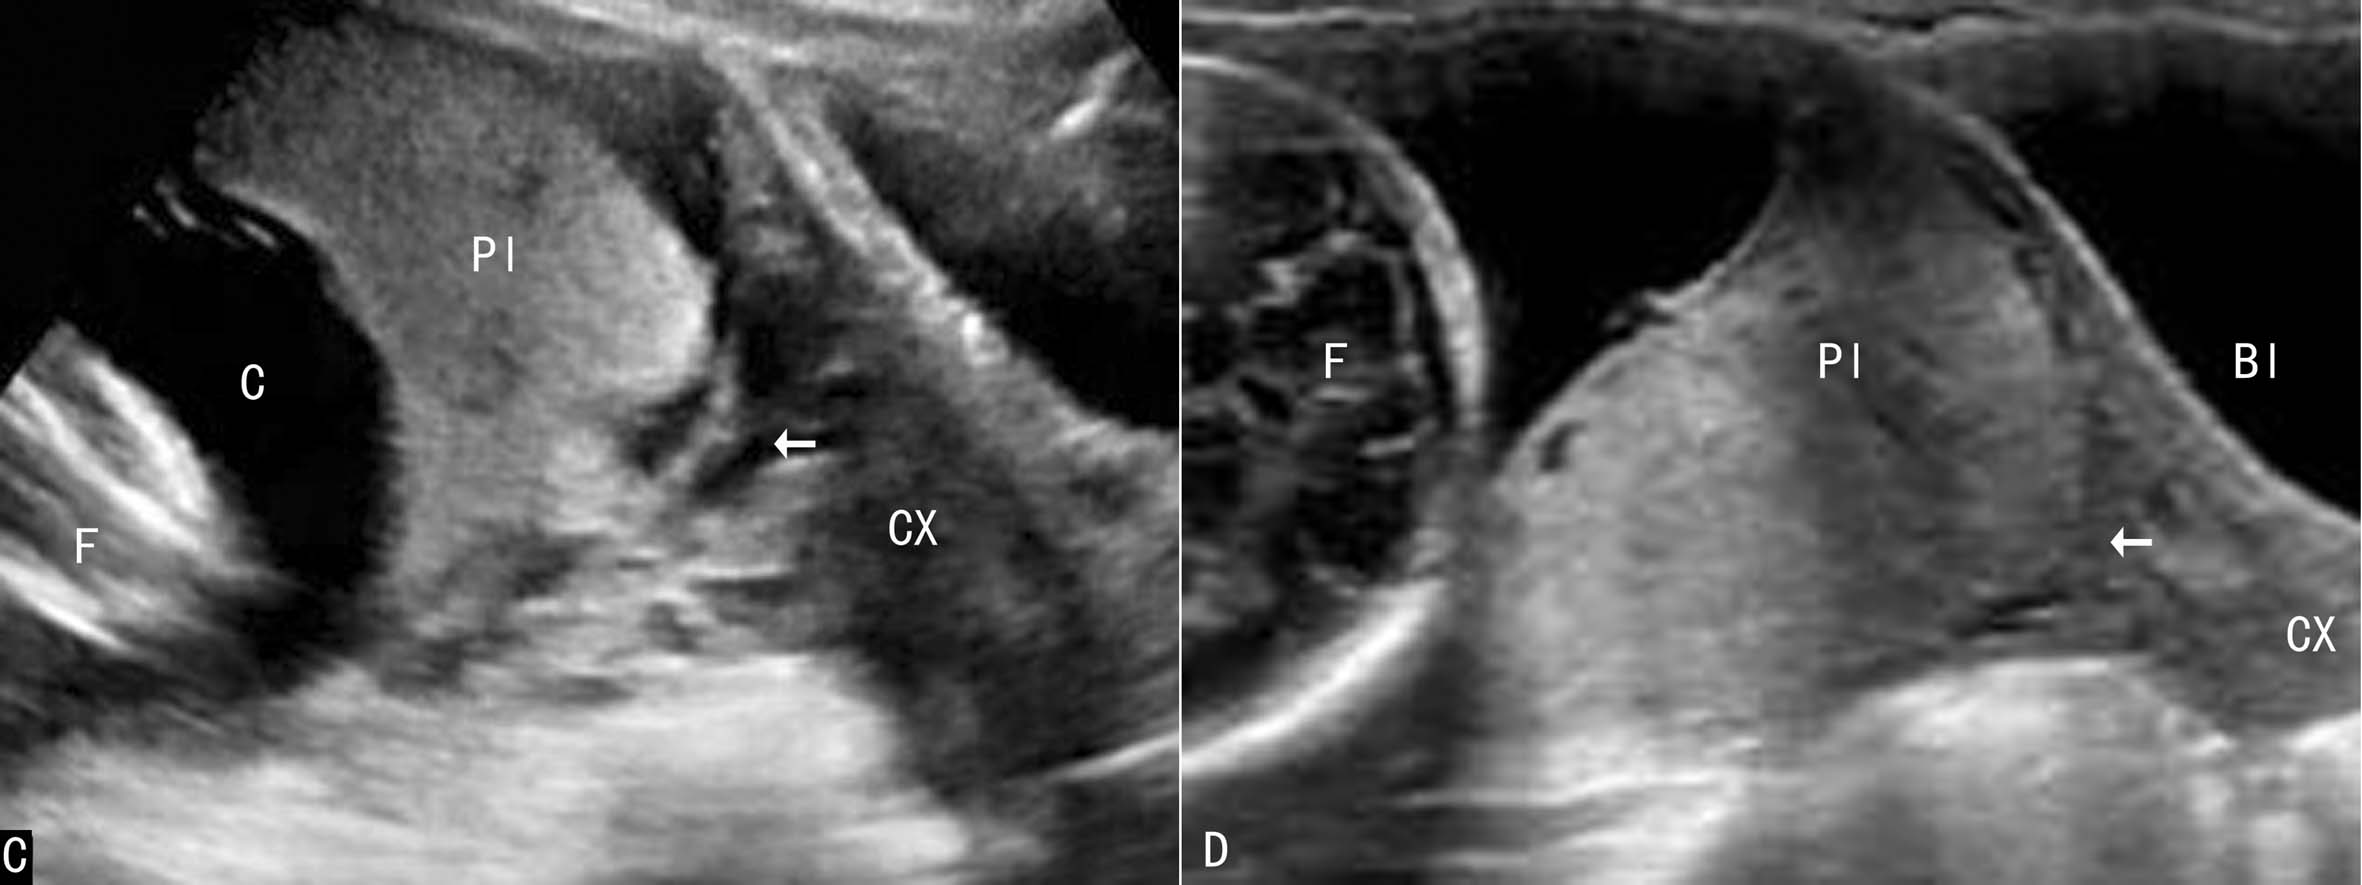

PL主体附着的位置正常,并不能完全排除异常形态的部分PLP。图3显示了一例副叶PL前置的孕妇声像图,PL主题位于子宫后壁,在子宫颈内口处显示一小块PL样组织。此种情况应当给予充分的注意,结合临床即可做出诊断,以避免阴道大流血的发生。

图3胎盘副叶前置声像图